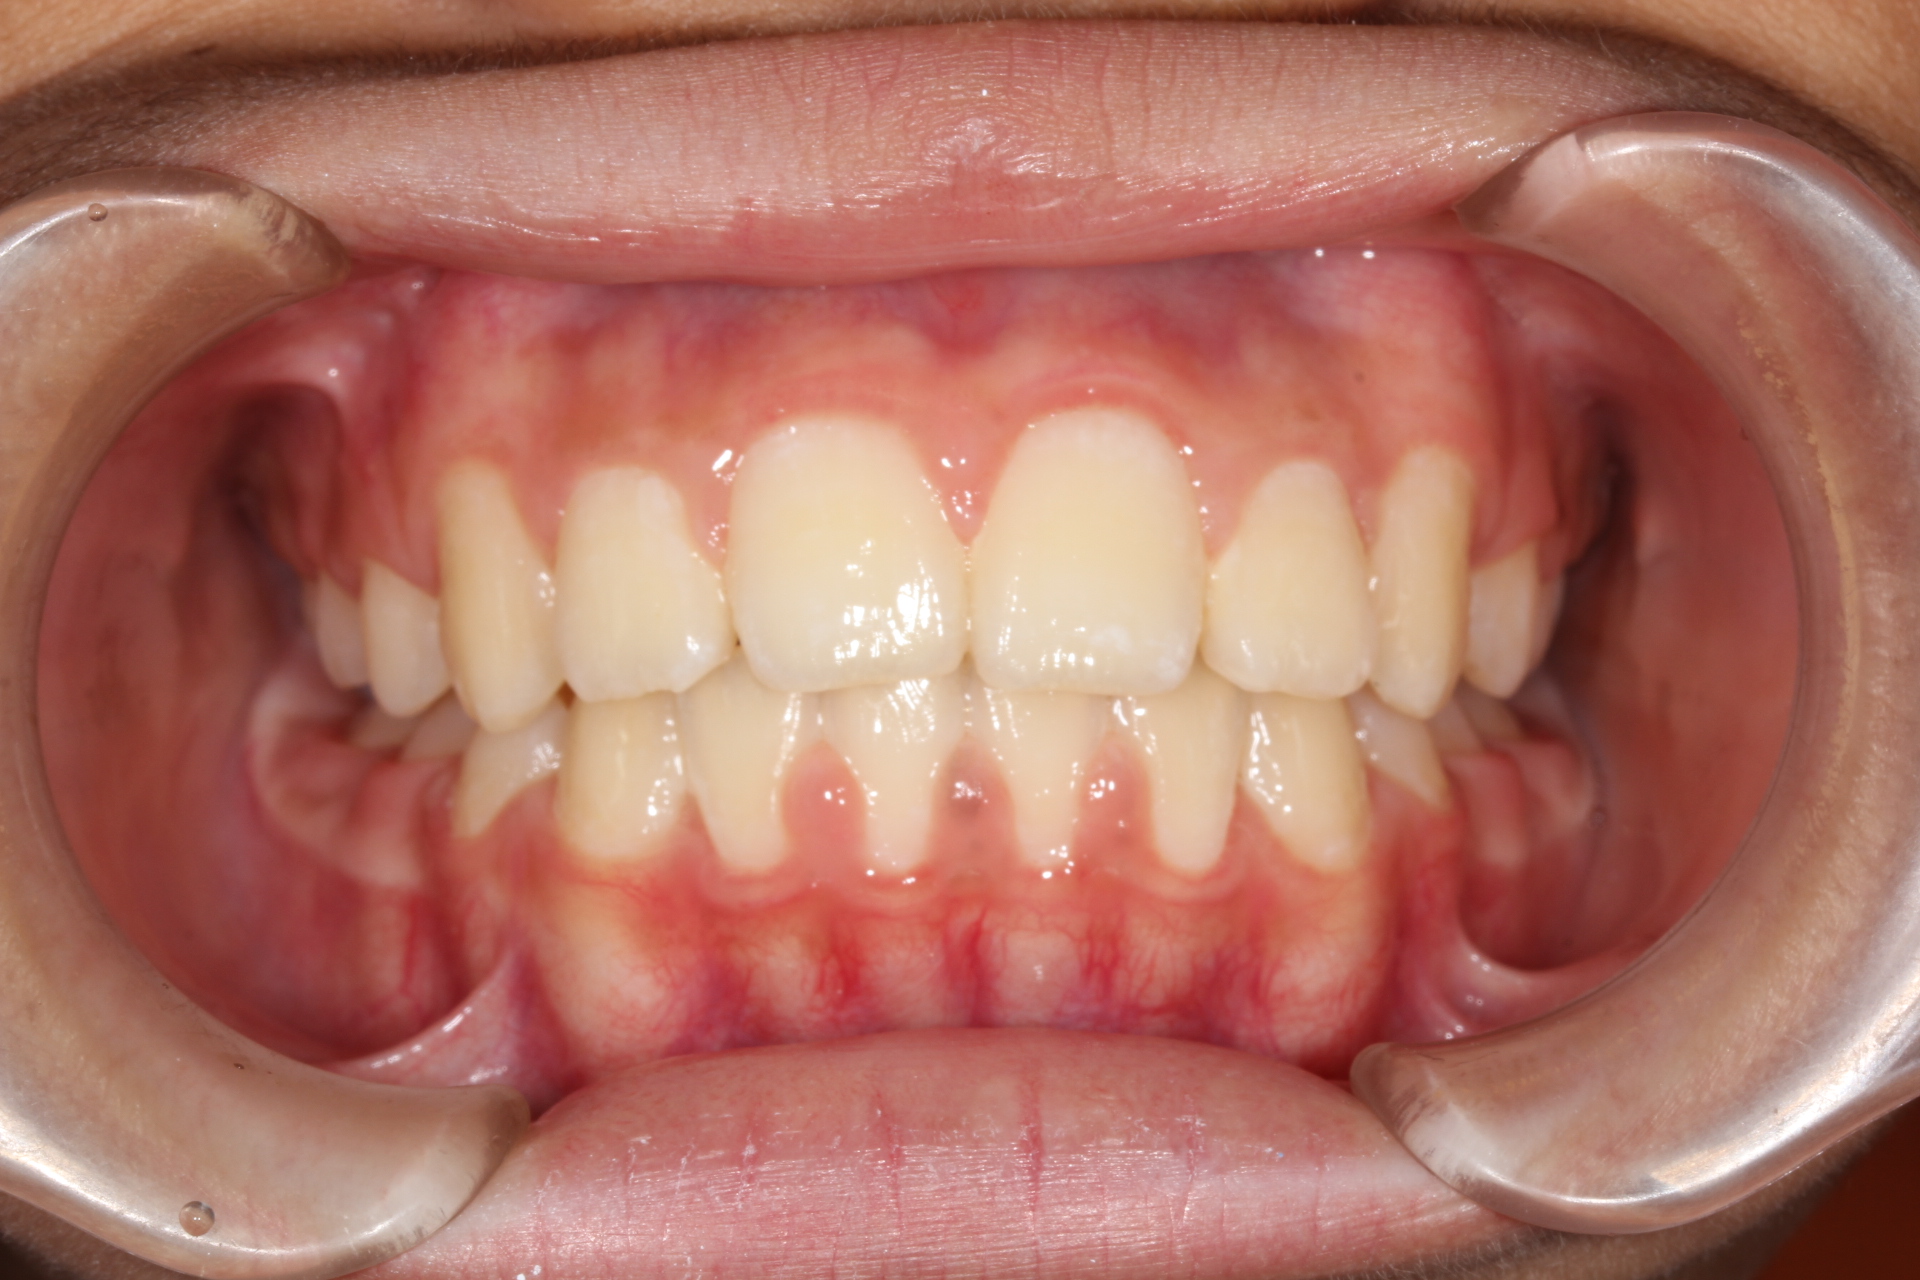

歯並びがキレイになった段階で、矯正装置を外します。

キレイな歯並びを維持するために、歯を安定させる装置を入れます。

キレイな歯並びが安定したら、治療は終了です。